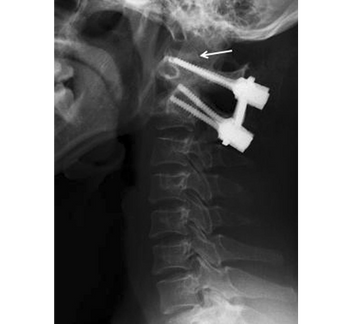

Posterior Atlanto-Axial Fusion

This procedure involves placing screws, rods, or wires to secure the atlas and axis together. The aim is to achieve permanent spinal stabilization while promoting bone fusion between the vertebrae, preventing further dislocation and neurological complications.